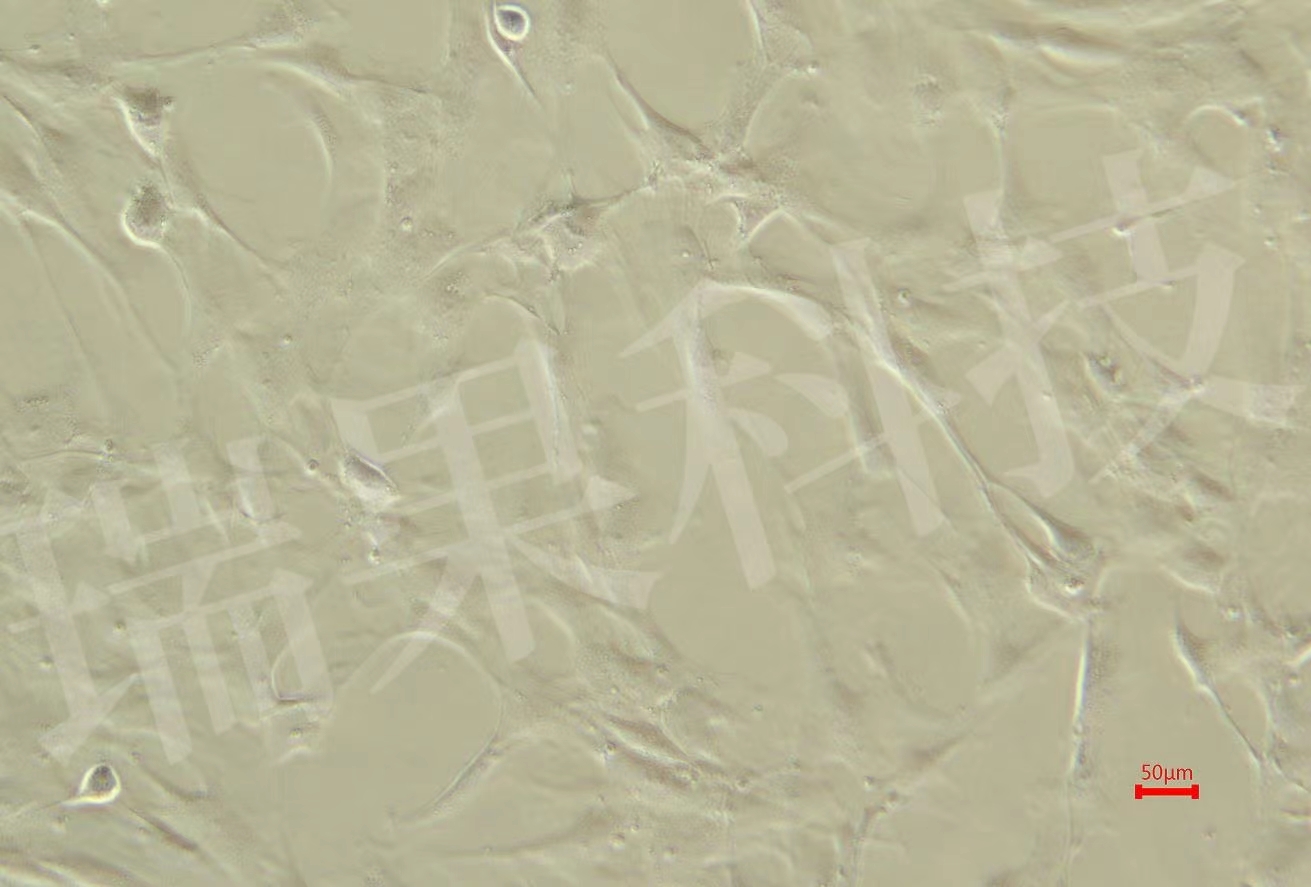

细胞周期是指细胞一个世代所经历的时间。从一次细胞分裂结束为一个周期。细胞周期反映了细胞增殖速度。单个细胞的周期测定可采用缩时摄影的方法,但它不能代表细胞群体的周期,故现多采用其他方法测群体周期,如BrdU掺入检测法。

BrdU(5-溴脱氧尿嘧啶核苷)加入培养基后,可作为细胞DNA复制的原料,经过两个细胞周期后,细胞中两条单链均含BrdU的DNA将占1/2,反映在染色体上应表现为一条单体浅染。经历了三个周期,赠染色体中约一半为两条单体均浅染,另一半为一深一浅。细胞如果仅经历一个周期,则两条单体均为深染。计分裂相中各期比例,就可以计算细胞周期的值。